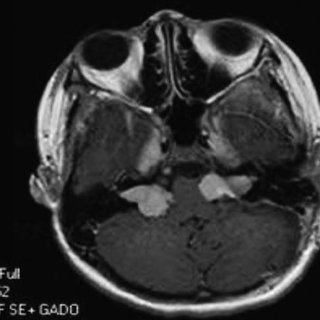

聽神經(jīng)瘤通常起源于覆蓋該神經(jīng)的雪旺細胞,生長緩慢或根本不生長。是什么導(dǎo)致了這種基因故障尚不清楚,在大多數(shù)聽神經(jīng)瘤病例中,沒有可識別的原因。磁共振成像使用釓作為增強...

掃描和測試的進步使得識別小型聽神經(jīng)瘤(仍局限于內(nèi)耳道)成為可能。磁共振成像使用釓作為增強對比材料是識別聽神經(jīng)瘤的優(yōu)選診斷測試。如果存在聽神經(jīng)瘤,所形成的圖像清楚地定義了它,并且這種技術(shù)可以識別直徑小至5毫米(掃描間隔)的腫瘤。